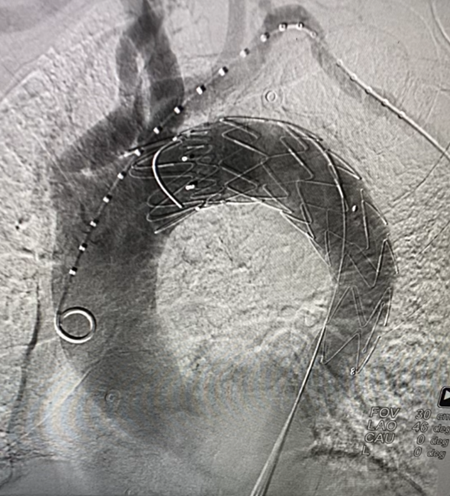

手术由邓捷主任医师、李永勤主任医师、张春艳主治医师、张明医师、张恒医师及介入治疗团队合作完成,在进行局部麻醉后,通过左侧桡动脉置入金标猪尾导管经左锁骨下动脉送至升主动脉,通过右侧股动脉植入覆膜支架,位置确认无误后释放支架。手术成功实施,历时约1个小时。术后患者恢复良好,按期出院。